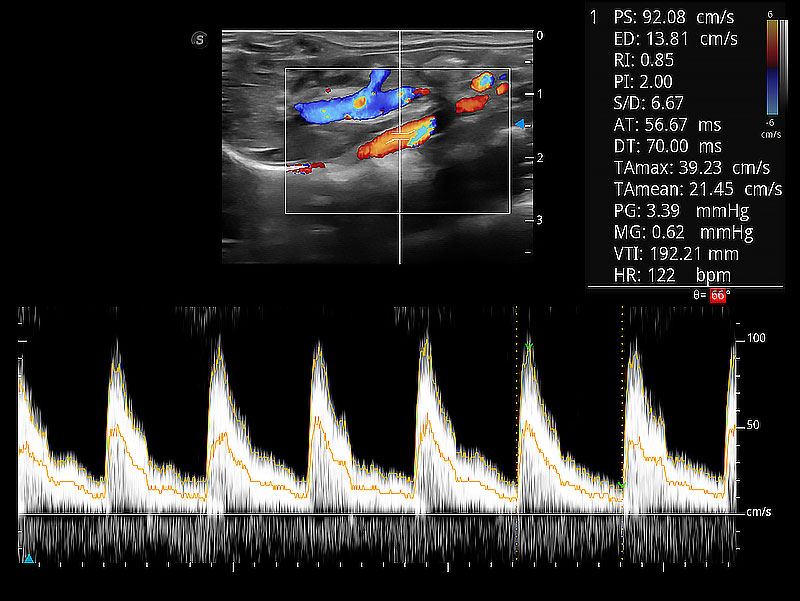

• Auto Trace 頻譜自動包絡(luò)

隨著取樣門位置改變,頻譜多普勒包絡(luò)可進(jìn)行自動眼蹤測量,且可自由配置測量的參數(shù)。

(犬)胎兒主動脈弓立體血流

(犬)二腔心血流